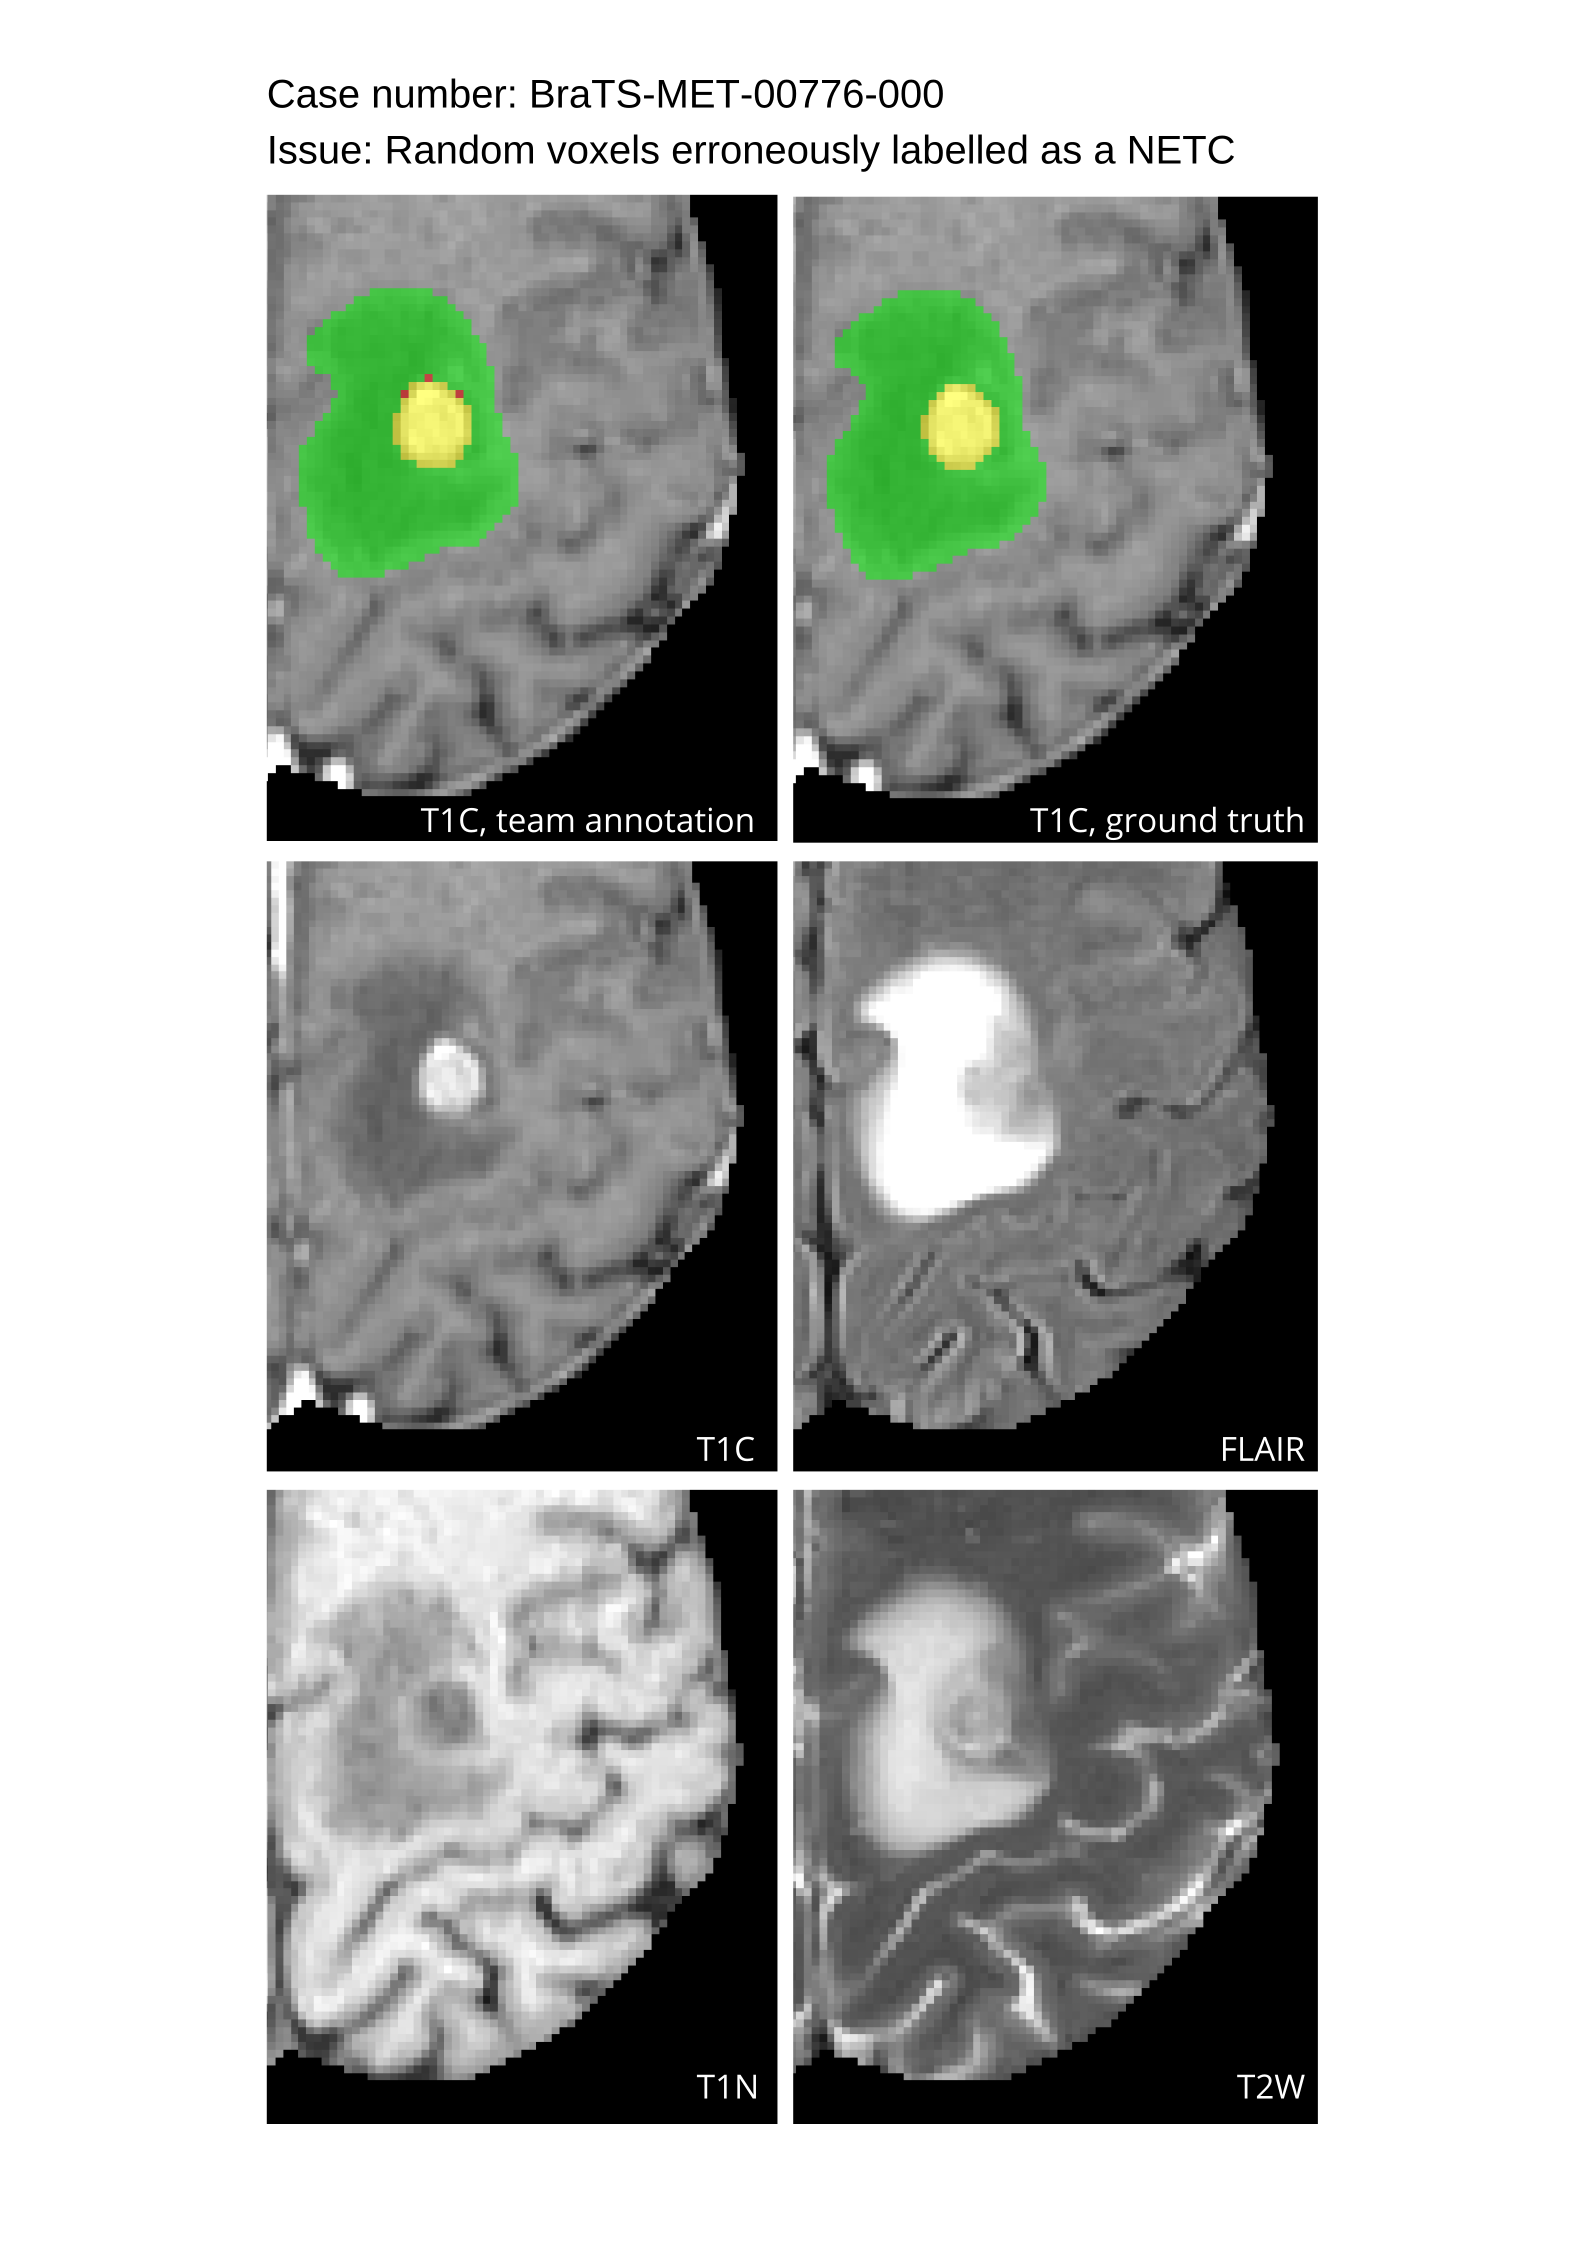

Approvers reviewed the volunteer annotations and either approved the case or returned it to students for re-annotation. Additionally, a QC process was implemented, which included removing all random voxels and any voxels outside the brain mask, ensuring all images had the same parameters (space, orientation, and origin) as the SRI24 atlas, and verifying the presence of all segmentations and segmentation masks are in the folder with original NIfTI images.

4.9 Common Errors of Automated Segmentations

Based on observations from previous BraTS challenges, common errors in automated segmentations were identified. The most typical errors in the current challenge included:

1. 1.

Automated algorithms missing small metastases. Enhancing metastasis was fused using the minority voting algorithm to aggregate all enhancing tumor voxels identified by the three algorithms. However, many small metastases were missed and were manually segmented by neuroradiology attendings.

2. 2.

Segmentation of white matter changes from microvascular disease. Peritumoral edema segmentations were checked by neuroradiology attendings and modified.

3. 3.

The segmentation of non-enhancing lesions that have intrinsic T1 hyperintensity. Voxels with intrinsic T1 hyperintensity were manually removed from ET segmentations.

These insights led to specific adjustments in the annotation process to enhance accuracy.